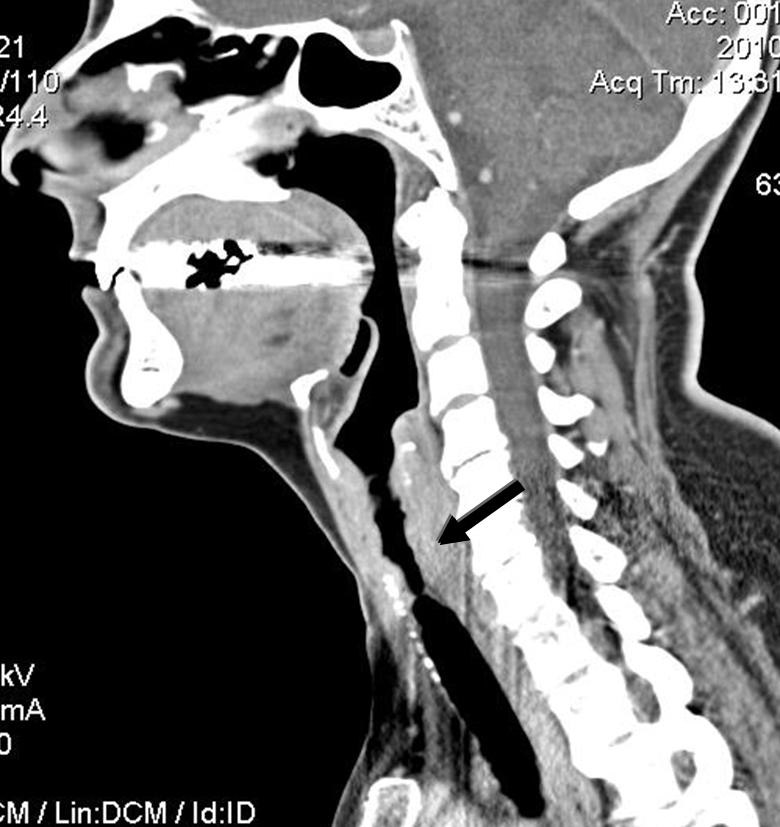

Figure 4

CT scan of the neck of a patient with GPA showing 6-cm-long subglottic stenosis (arrow).

SGS is best studied on CT scan (fig. 4 and 5) but must also be evaluated clinically by flexible nasolaryngoscopy. Interestingly, the lesion is usually segmental and located 1 to 2 cm below the vocal cords, probably because it represents the junction between 2 embryological buds or growth centres. Biopsy of the lesions can be revealing in more than half of cases, but endoscopy and biopsy of SGS may be risky in such patients. These invasive procedures can trigger a local inflammatory reaction, worsen the stenosis, and/or result in detached necrotic debris which is then inhaled, during the procedure itself or soon after. Spirometry may reveal blunting of the inspiratory curve, but the diagnosis should not rely solely on this modality.